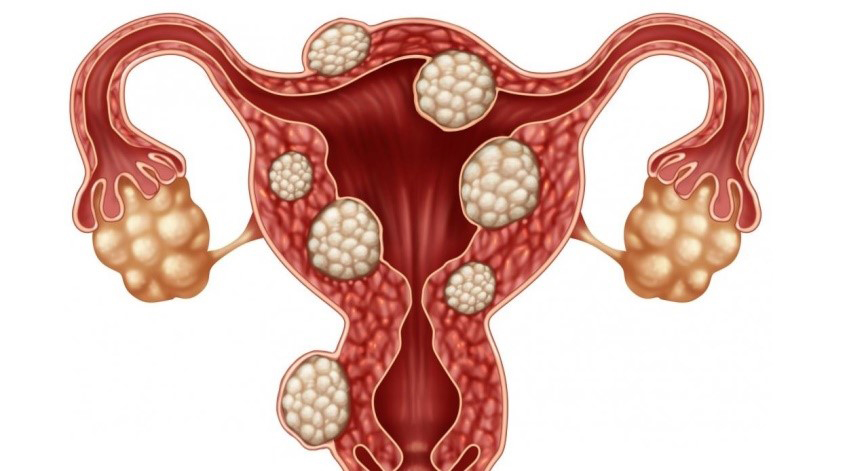

قیمت: 52٬500 تومان - دسته بندی فایل: پاورپوینتدانلود پاورپوینت مطالعه فیبروم رحم

خرید پاورپوینت حرفه ای با موضوع مطالعه فیبروم رحم با قیمت استثنایی از لوکس فایل